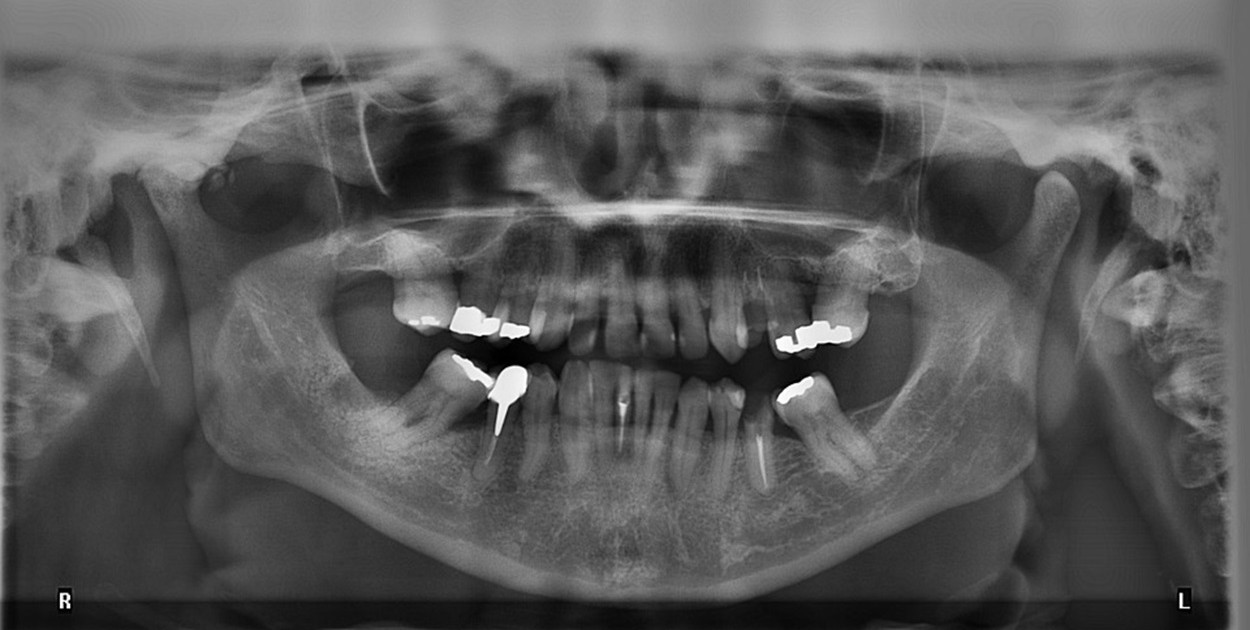

Pantomogram, znany także pod nazwą pantomografii, jest kluczowym badaniem w radiologii stomatologicznej i ortodoncji, oferującym wszechstronną analizę stanu jamy ustnej, a także struktur anatomicznych głowy i szyi. Jest to podstawowe narzędzie diagnostyczne, które pozwala na dokładną ocenę i identyfikację najlepszego planu leczenia wad zgryzu już podczas pierwszej konsultacji ortodontycznej, bazując na szczegółowym obrazie i ocenie stanu zdrowia jamy ustnej pacjenta.

Pantomogram to specyficzny typ badania rentgenowskiego, który zapewnia szczegółowy przekrój struktur anatomicznych obszaru jamy ustnej, w tym żuchwy i kości skroniowej. Dzięki swojej nieinwazyjności i bezbolesności, badanie to stanowi bezpieczną metodę dla lekarzy do przeprowadzenia kompleksowej oceny zdrowia jamy ustnej oraz sąsiadujących z nią kości i tkanek.